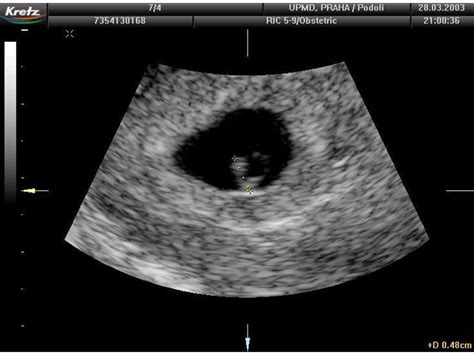

V 9. týždni tehotenstva, ktorý sa nachádza na konci 3. mesiaca a v prvom trimestri, embryo meria približne 20-40 mm a váži 2-3 gramy. Je stále pomerne malé, prirovnávané k arašidu alebo stredne veľkej olivke. Hlavička je neúmerne veľká v porovnaní s telom, ale jej rast sa spomaľuje, zatiaľ čo telo začína rýchlejšie rásť. Formuje sa brada, nos je viditeľný z profilu, objavujú sa ústa s vrchnou perou, vyvíja sa vnútorné ucho a sformované sú základy mliečnych zubov.

Oči sa vyvíjajú, čiastočne obsahujú pigment a sú zakryté viečkami, ktoré sa otvoria až neskôr. Srdiečko bije rýchlosťou 130-150 úderov za minútu. Vyvíjajú sa kľúčové orgány ako pankreas, pečeň (ktorá produkuje krvné bunky), obličky, pľúca a srdce, ktoré sa rozdelilo na štyri časti. Mozog sa zdokonaľuje, vytvárajú sa neurónové spojenia a začína riadiť funkciu orgánov. Formuje sa bránica, ktorá oddelí hrudnú a brušnú dutinu.

Črevá rastú a postupne sa presúvajú z pupočnej šnúry do brušnej dutiny. Chvostík na konci tela mizne, zatiaľ čo sa formuje kostra a rebrá. Prsty na rukách a nohách sú viditeľné, ohýbajú sa ruky v lakťoch a kolenách. Dieťatko sa začína reflexívne pohybovať, čo stimuluje vývoj svalstva. Tieto pohyby sú na ultrazvuku viditeľné, no matka ich ešte necíti.